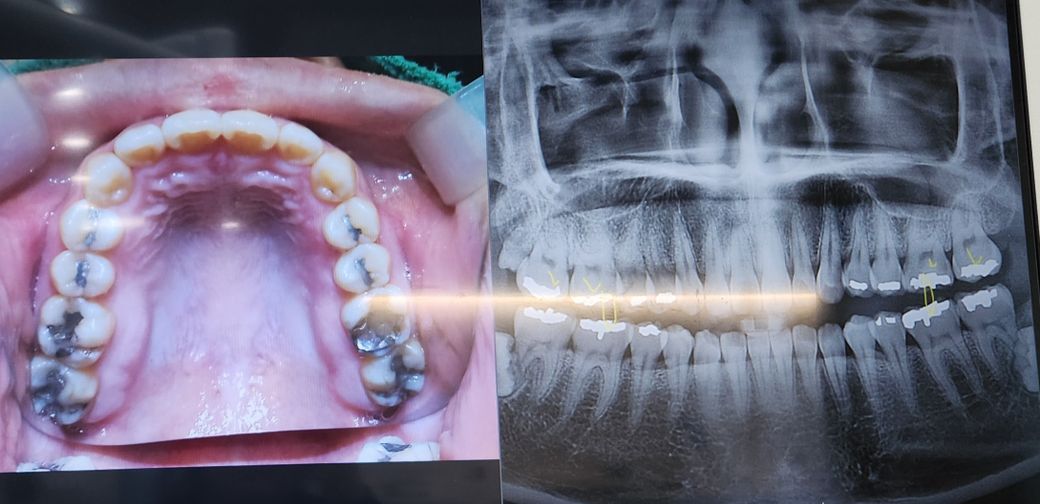

어금니인데 병원에서는 레진으로 해주실수있다 했는데 레진 괜찮나영?

이가 저래서 아는언니 한테 물어보니 저정도면 인레이이 낫지않나 하는데..

어금니쪽 아말감으로 때운게 떨어져서 그거를고칠려고 물어보니

제가 고민인 부분이 어금니쪽이고

범위가 꽤 큽니다. 저정도는 전체적으로 씌우는 크라운 해야 할 가능성도 있습니다. 레진은 추천하지 않습니다.

레진으로 한다고 잘 부러지거나 떨어지진 않습니다만 현재 수복범위를 볼 땐 크라운을 할 것 같긴합니다.

사진으로 봤을 경우에는 이전에 아말감으로 메꾼 부위와 충치의 부위가 넓어 보입니다이 정도 크기라면 레진으로 치료를 하는 것보다 크라운이라는 보철 치료를 하는 것이 더 좋습니다 자세한 확인을 위해서 치과에서 진료를 받아 보는 것을 권해 드립니다

아말감 부분이 너무 넓어서 레진보다는 최소 인레이나 크라운 치료를 하셔야될것같습니다.